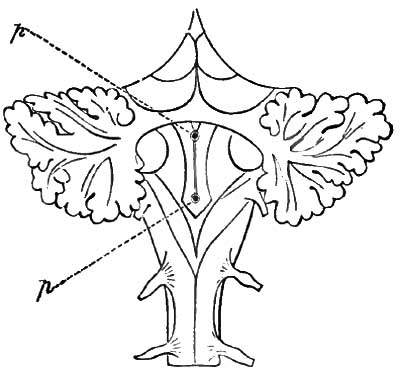

| 1. | POSITION OF PUNCTURES IN DIABETIC AREA OF MEDULLA OBLONGATA NECESSARY TO PRODUCE GLYCOSURIA |